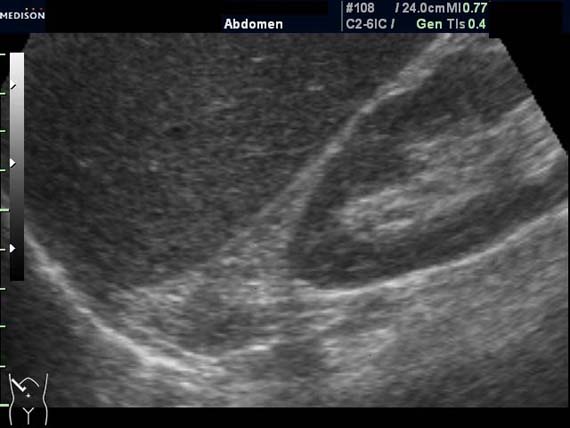

Женщина 50 лет. Жалоб нет. Обследование перед поездкой в санаторий по поводу дисфункции гепатобилиарной системы.

Случайная находка в нижней трети левой почки (не в полюсе, а по задне-медиальной поверхности).

Образование в левой почке

ПО УЗ-семиотике образование соответствует ангиомиолипоме (AML). По правилам в таких случаях необходимо выполнить КТ, доказать преимущественно жировой состав опухоли, затем проводить УЗ-наблюдение.

Согласен. Именно с таким диагнозом (ангиомиолипома) отправил на КТ. Особенностью случая ИМХО является заметный "выход" образования за контур почки (на 2/3 объема).

При ультрасонографии ангиомиолипома выглядит как округлое образование без капсулы с однородной внутренней эхоструктурой и четкими контурами; эхогенность ее чаще всего равна или чуть выше эхогенности перинефральной клетчатки [7]. Значительно реже эхогенность ангиомиолипом может быть равна эхогенности почечной паренхимы; такие опухоли состоят почти полностью из гладкомышечной ткани [8]. Иногда позади ангиомиолипомы может определяться слабая акустическая тень.